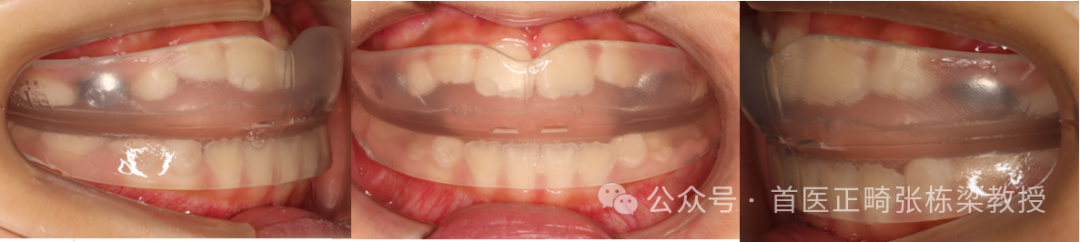

因此此时如果孩子能配合的话,我也会给他们做Grace个性化定制的硅胶牙套,这个比较薄,孩子戴着也舒服,而且佩戴时间短,也不会对孩子牙齿产生损耗,还能锻炼孩子的正确舌位习惯,同时辅助舌肌训练,几个月就能有好的变化。